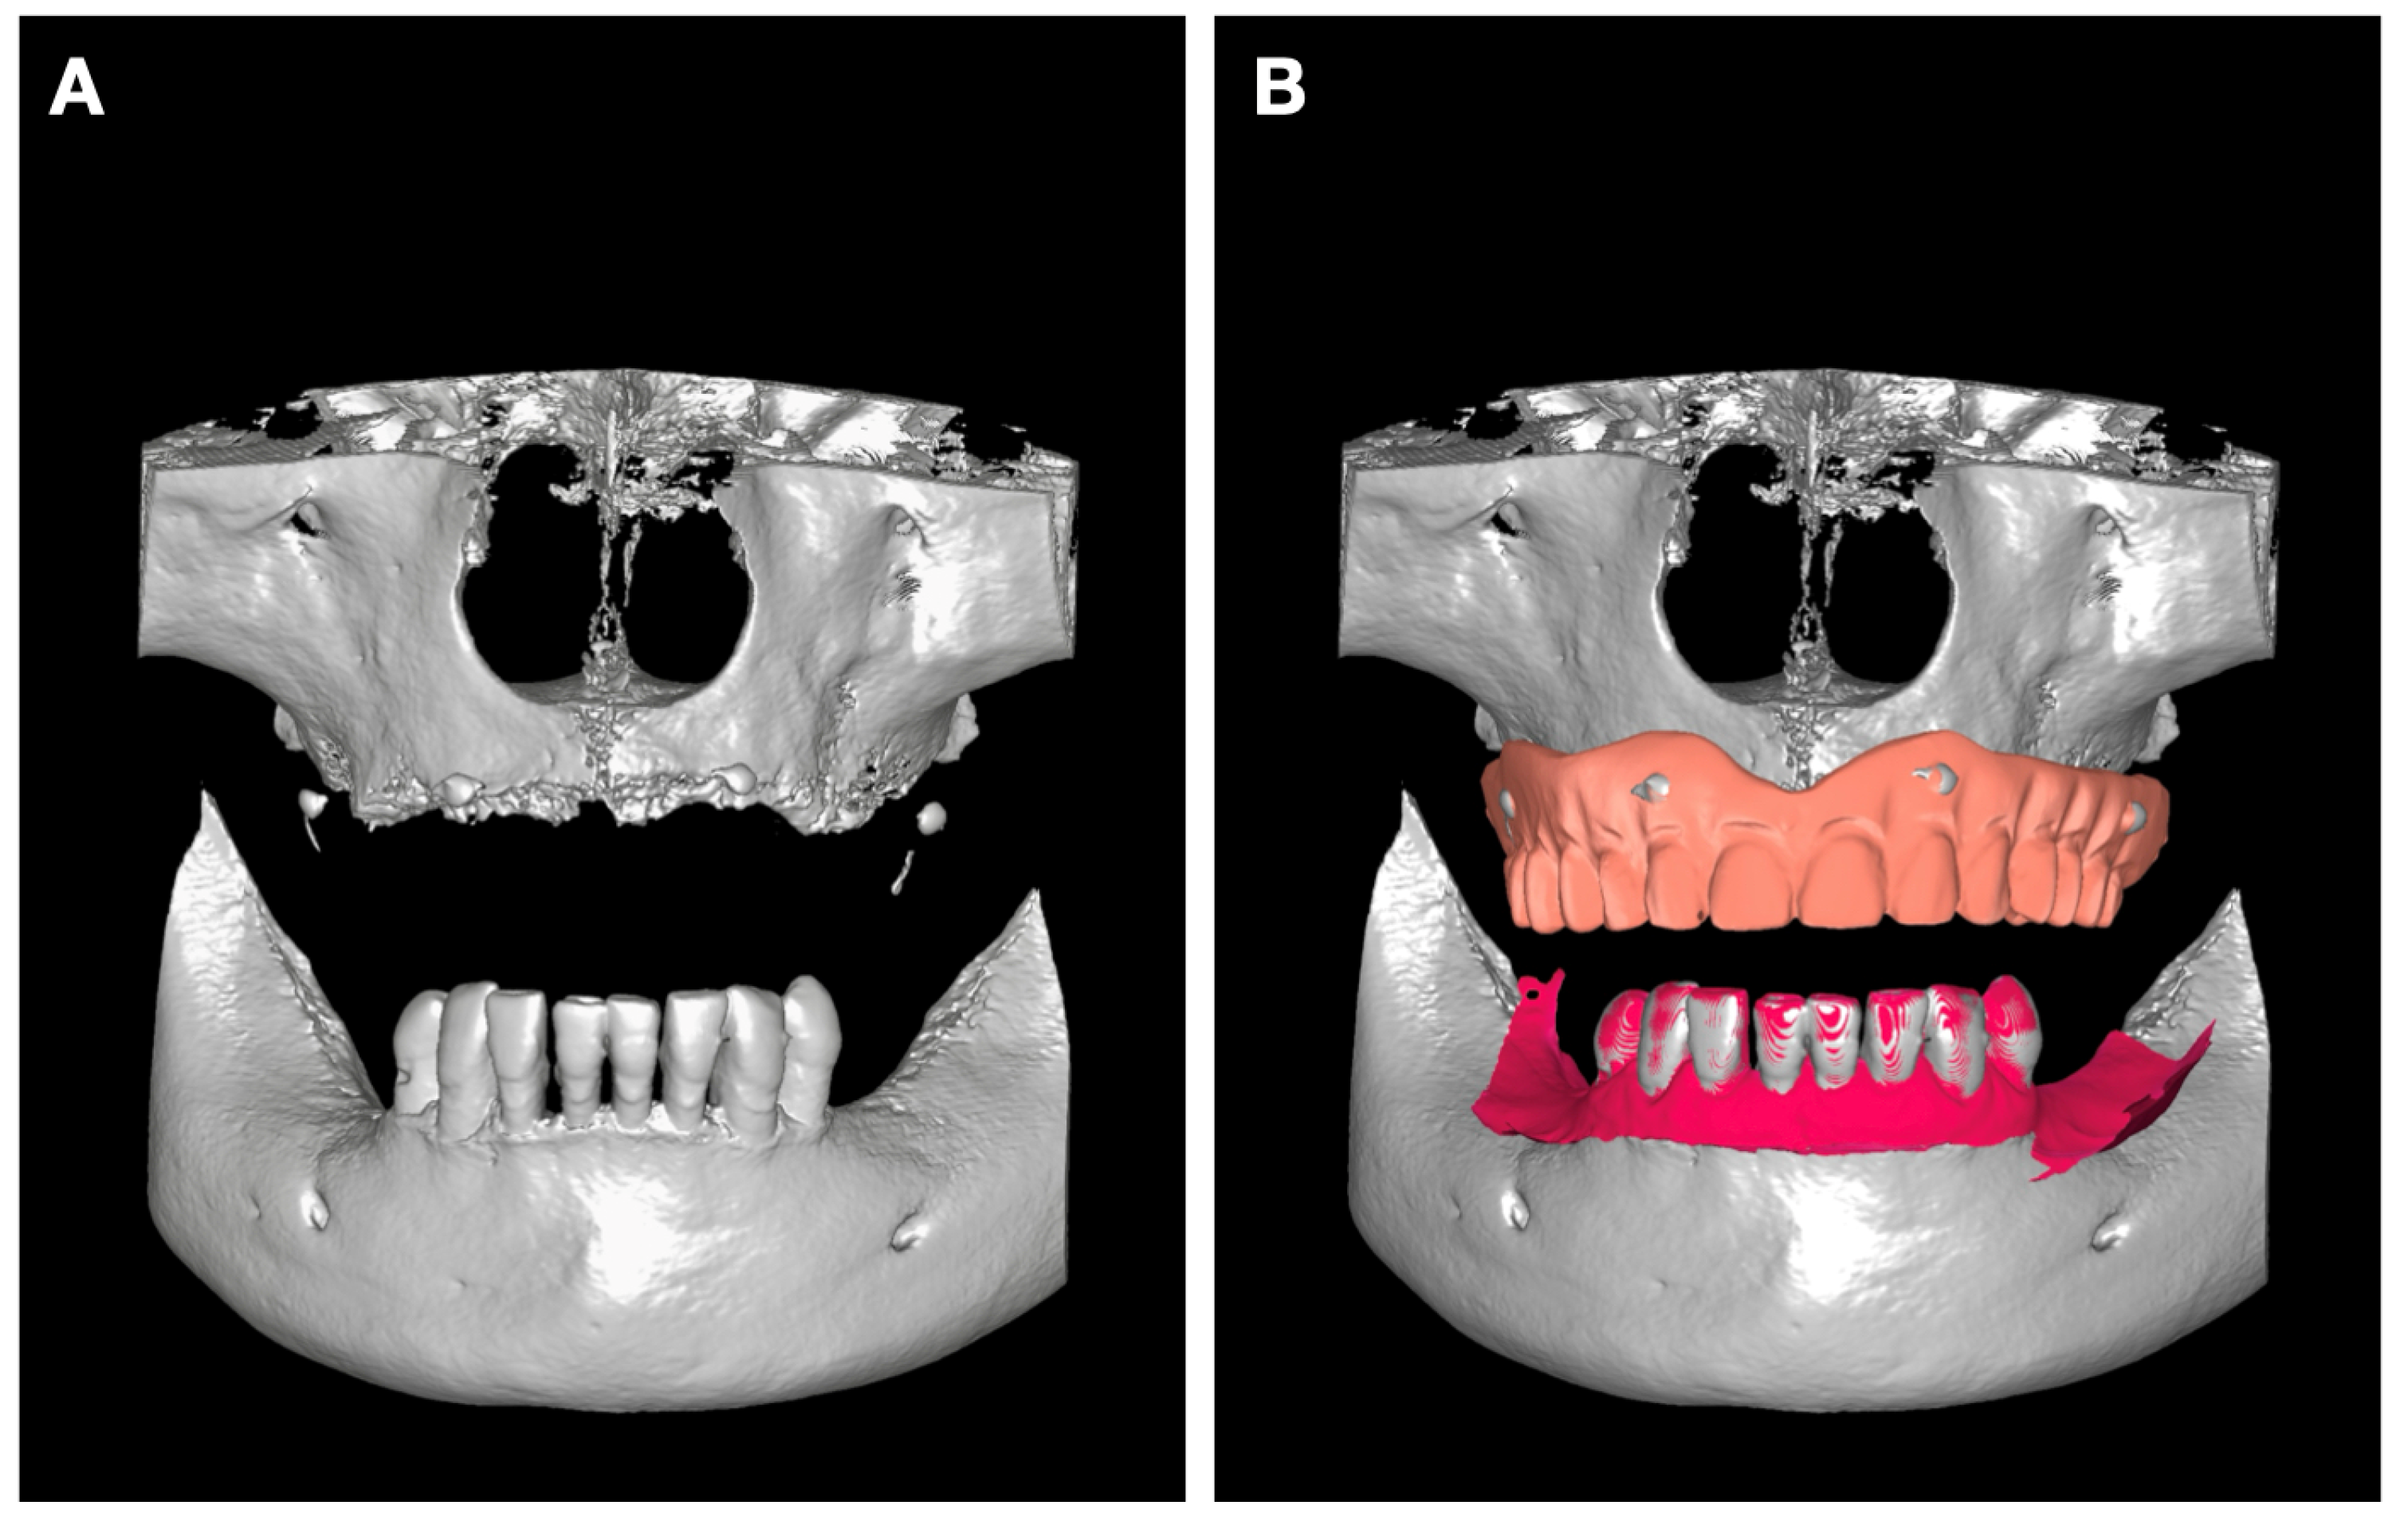

The STL files were aligned with CBCT data through radiopaque marker registration using the Implastation software (ProDigiDent, Batavia, IL, USA) (Figure 3B). We first aligned the markers and then verified, in both axial view and cross-section, that the contour of the prosthesis acquired by optical scanning matches that provided by CBCT.

Immediately after surgery, scan bodies were mounted on the MUAs, and an intraoral scan was performed to capture the definitive three-dimensional position of the implants. This scan was then superimposed with the scan of the patient’s initial complete denture, creating a single digital model that accurately represented the postoperative prosthetic situation (Figure 10A).

In parallel, the initial virtual plan created in Implastation (Figure 10B) displayed the pre-planned implant positions together with the corresponding MUAs, scan bodies, and the prosthetic setup designed from the initial denture.

Comparison of the postoperative superimposed scan (Figure 10A) with the preoperative digital simulation (Figure 10B) revealed a clear positional correspondence between the planned and the actual implant trajectories. The implant emergence profiles aligned with the intended prosthetic axes, confirming that the guided osteotomy protocol accurately transferred the digital plan to the clinical setting.

Figure 3. (A) 3D reconstruction from CBCT; (B) overlay of intraoral scans on the CBCT reconstruction. The maxillary prosthesis was overlaid using radiopaque markers, while the lower arch scan was aligned using dental units as references.

Figure 10. (A) Overlay of the initial prosthesis and edentulous field scans onto the dental implant position scan; (B) implant planning in Implastation, including implants, multi-unit abutments, and scan bodies.